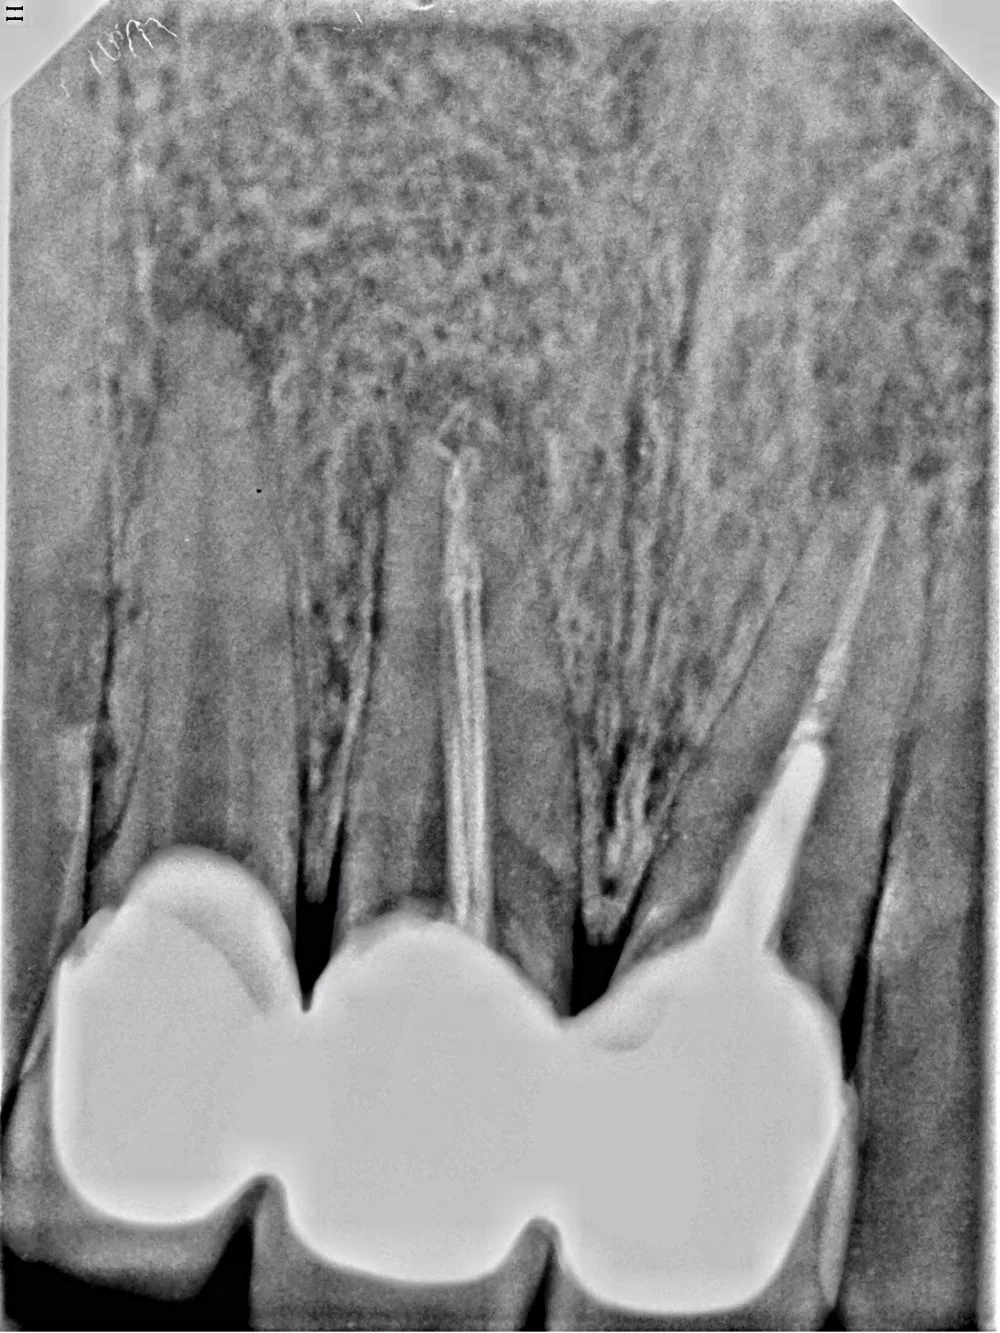

High Resolution HDR600 Dental Xray Sensor/Size 2 Intraoral Sensor with TWAIN Driver

aliexpress.com